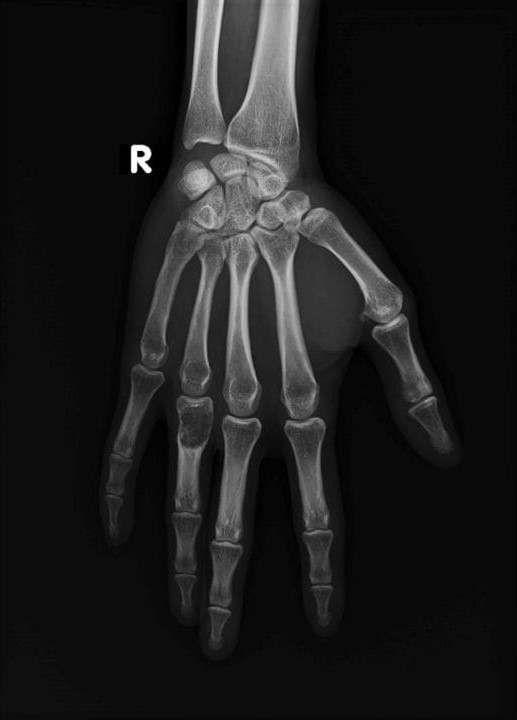

انکندروم رایج‌ترین تومور دست محسوب می‌شود و بیشتر، استخوان‌های کوچک را درگیر می‌کند. در موارد نادر ممکن است در استخوان ران، بازو یا ساق نیز دیده شود.

انکندروما اغلب به‌صورت تصادفی، در حین انجام تصویربرداری برای آسیب‌دیدگی یا بیماری‌های دیگر مانند آرتروز، تشخیص داده می‌شود.

برای اطمینان از خوش‌خیم‌بودن تومور، پزشک ابتدا شرح‌ حال دقیق و معاینه فیزیکی انجام می‌دهد و سپس از روش‌هایی مانند رادیوگرافی، سی ‌تی ‌اسکن یا MRI کمک می‌گیرد.

در رادیوگرافی، تومور معمولاً به‌صورت توده‌ای لوب‌دار با نقاط سفید نمایان می‌شود. در موارد خاص، اسکن استخوان یا نمونه‌برداری (بیوپسی) نیز ممکن است انجام شود تا تومورهای تهاجمی یا بدخیم افتراق داده شوند.